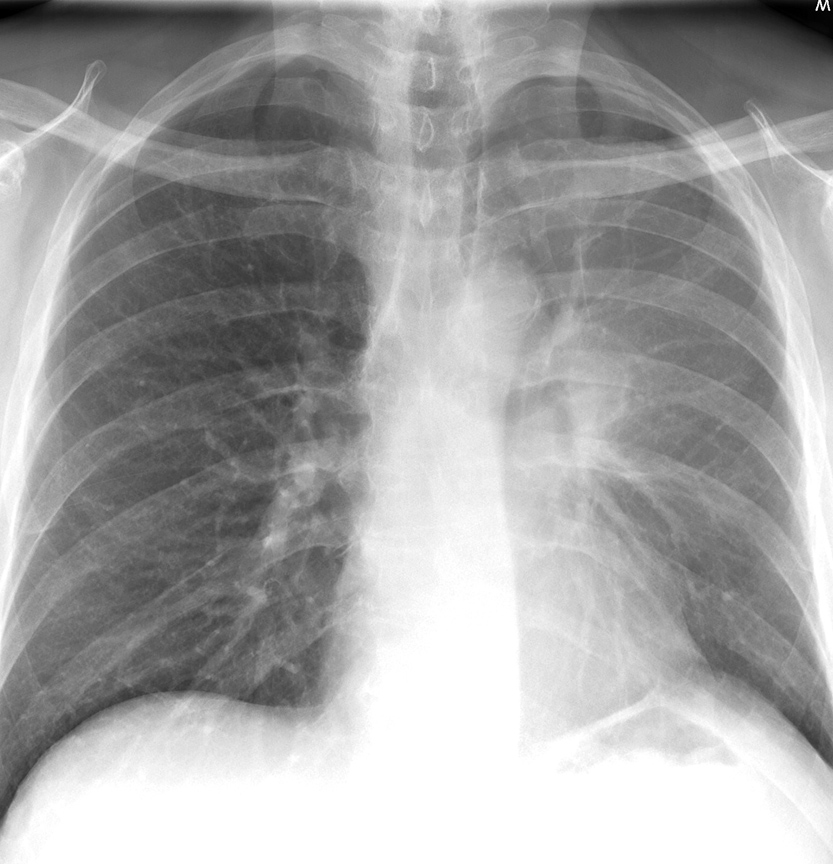

LUL collapse Case10